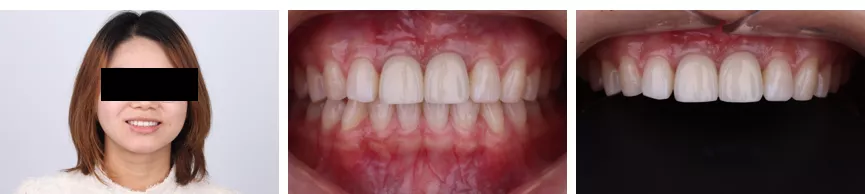

半年后复查

·       患者在历经一年多的前牙种植修复治疗后,得到了总体较好的功能修复和美观效果。病历总体达到了预期的治疗效果,患者较为满意。

·       稍显不足的是在患者佩戴了最终修复体后,龈缘高度的对称性还存在一些偏差。并且右侧袖口相比左侧的效果稍显不足。由于患者在治疗期间由于工作变动和疫情的因素,临时牙佩戴时间较长发生了几次断裂,损伤了穿龈袖口部软组织并且影响了牙龈塑形,可能是导致最终效果稍有偏差的主要因素。随之进行额外的软组织手术将卵圆形牙齿变为方圆也许会获得更加的红白美学效果。

·       最后,病历完成时间较短,后续的粉色美学效果理应会有所改善,期待后续定检。